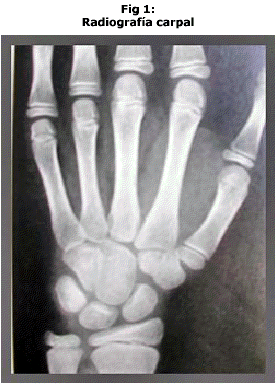

Para la determinación de la maduración ósea (edad ósea) se realizaron radiografías carpales de la mano contralateral a la usada con mayor frecuencia.(Fig 1) Para ello se utilizó un tiempo de exposición de 1,5 segundos y una angulación vertical de 90º perpendicular al plano de proyección.

3º etapa: el examen e interpretación de las películas se realizó con luz blanca y magnificación idénticas ( 2 X). Las imágenes de la radiografía carpal fueron comparadas con otras consideradas como standars e incluidas en el Atlas Radiográfico de Desarrollo Esqueletal de Manos y Muñecas de Greulich and Pyle, 1959 (5). Las imágenes del canino inferior fueron comparadas con la Tabla de Fases de Desarrollo Dental adaptado por Haavikko, que clasifica la edad dentaria según la fase de mineralización de los elementos dentarios.